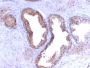

This antibody recognizes a single protein of 33-34 kDa, identified as the prostate specific antigen (PSA). This MAb is highly specific to PSA and stains prostatic secretory and ductal epithelium in both normal and neoplastic tissues. PSA is a chymotrypsin-like serine protease (kallikrein family) exclusively produced by the prostate epithelium, and abundant in seminal fluid. PSA can be detected in the sera of patients with prostatic carcinoma. It is predominantly complexed to a liver-derived serine protease inhibitor, alpha-1-antichymotrypsin (ACT). A higher proportion of serum PSA is complexed to ACT in prostate cancer than in benign prostate hyperplasia. This MAb makes an excellent pair with MAb A67-B/E3 for PSA tests.

PC12 cells or normal prostate or prostate carcinoma

IHC, FFPE (verified)

Higher concentration may be required for direct detection using primary antibody conjugates than for indirect detection with secondary antibody|Immunohistology (formalin): 0.5-1.0 ug/mL for 30 minutes at RT|Staining of formalin-fixed tissues is enhanced by boiling tissue sections in 10 mM Tris with 1 mM EDTA pH 9.0 for 10-20 minutes followed by cooling at RT for 20 minutes|Optimal dilution for a specific application should be determined by user